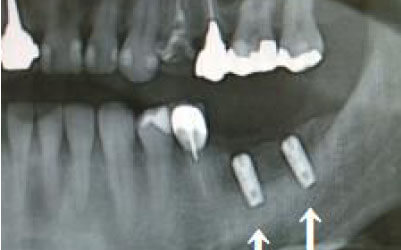

CTを使うことで、骨や歯の状態を3Dで確認でき、正確な距離測定も行えます。

骨の厚さや傾き、神経の位置などを事前にしっかりと計測することで、安全にインプラント治療を行うことができます。

2 神経を傷つけるリスク

インプラント治療では、顎の骨内に通っている神経を傷つけるリスクがあります。

しかし、事前にCTを撮影し、三次元的に神経までの距離を計測して治療計画を立てれば、心配することはありません。

また、過剰に削らないようにストッパーも使用しているため、安全に治療が進められます。